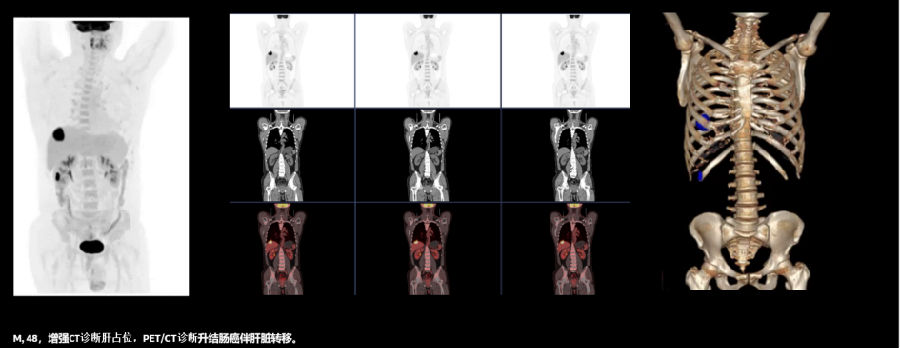

1、肿瘤的筛查和诊断

PET/CT在早期发现肿瘤的原发、转移和复发病灶等方面具有绝对优势,无论肿瘤细胞跑到哪里, 都能被PET/CT成功追踪定位,堪称追踪肿瘤的“生命雷达”。